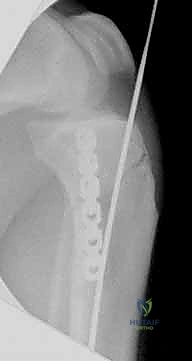

- التثبيت التشابكي (Interlocking): يتم تمرير مسامير صغيرة عرضية عبر العظم والمسمار النخاعي في الطرفين العلوي والسفلي، مما يمنع دوران العظم حول المسمار ويحافظ على طول الساق الطبيعي بدقة متناهية.

4. إدخال المسمار النخاعي والتثبيت النهائي

يتم تمرير مسمار التيتانيوم بدقة داخل العظم. وبمجرد التأكد من موضعه المثالي بالأشعة، يقوم البروفيسور هطيف بإدخال المسامير التشابكية (Locking Screws) العرضية في أعلى وأسفل المسمار لضمان التثبيت المطلق.